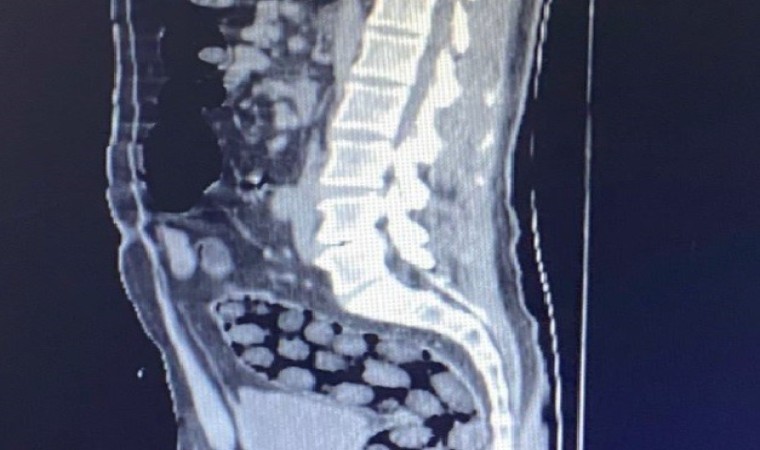

Bitlis Valiliğinden yapılan açıklamada, uyuşturucu ile mücadele kapsamında elde edilen istihbari bilgiler doğrultusunda Tatvan’da durdurulan bir otobüste yabancı uyruklu 3 yolcunun yakalandığı belirtildi. Açıklamada, “Bitlis Emniyet Müdürlüğü Narkotik Suçlarla Mücadele Şube Müdürlüğü ve İstihbarat Şube Müdürlüğü ekiplerince gözaltına alınan ve Tatvan Devlet Hastanesine sevk edilen şüphelilerin röntgen ve tomografi görüntülerinde mide ile bağırsaklarında çok sayıda yabancı cisim bulunduğu tespit edilmiş, yapılan tıbbi müdahale ile şüphelilerin paketleyerek yuttuğu toplam 91 adet daralı ağırlığı 1 kilo 126 gram metamfetamin maddesine el konulmuştur. Şüpheliler, çıkarıldığı adli mercilerce tutuklanarak cezaevine gönderilmiştir. Hemşehrilerimizin huzuru ve güvenliği için uyuşturucu madde imalatı, kaçakçılığı ve kullanımına karşı yürütülen kararlı mücadelemiz devam edecektir” denildi.